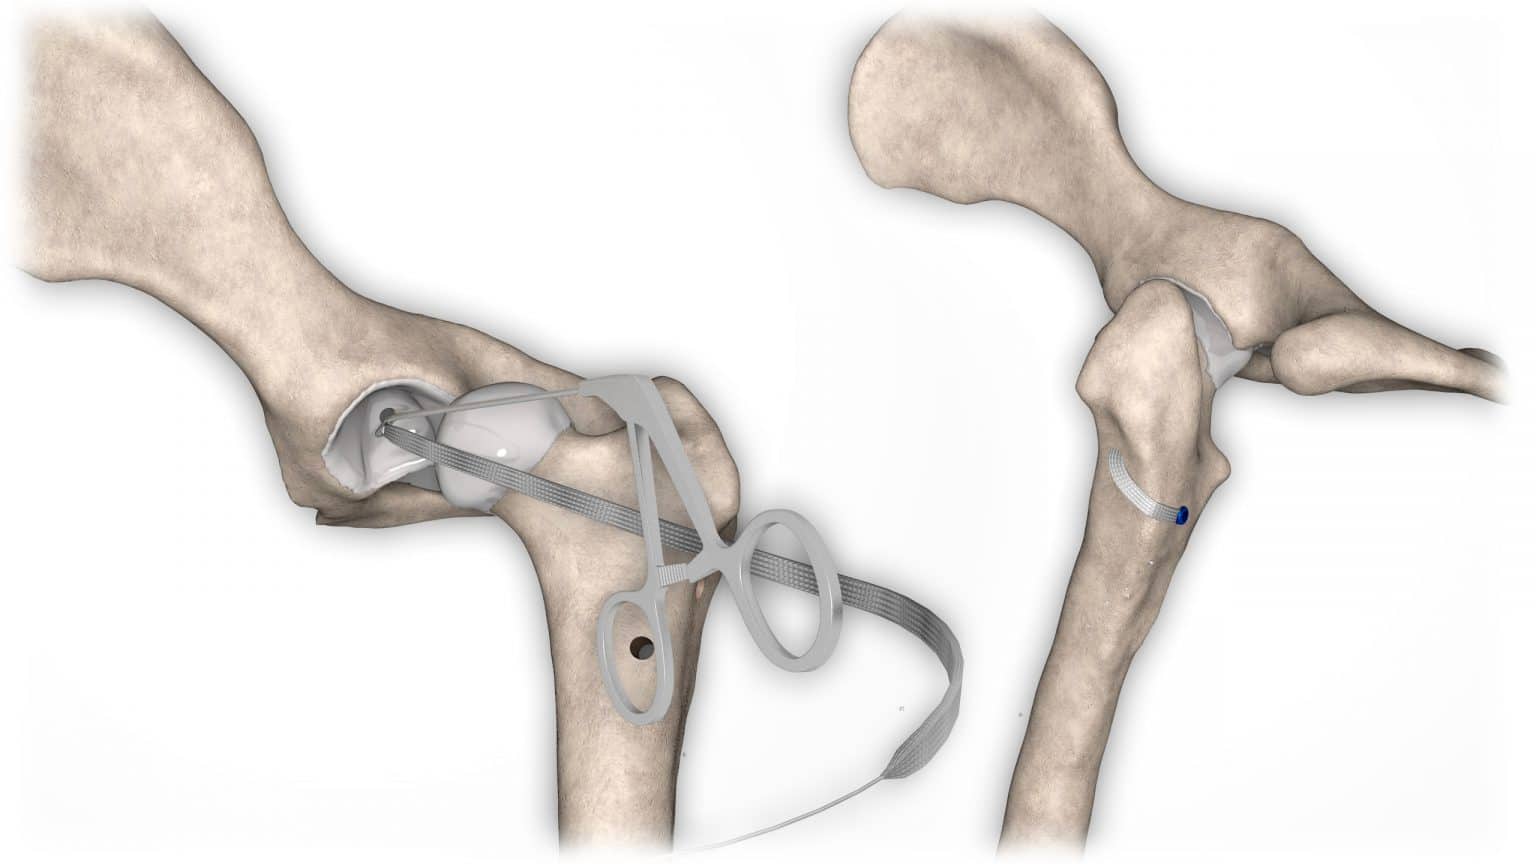

V případě ruptury kraniálního zkříženého vazu umožňuje ExtraTape® extraartikulární rekonstrukci co nejblíže izometrii původního vazu, čímž rychle a trvale stabilizuje koleno bez uzlů a zvlnění, což je slabina tradičnějších technik extraartikulární stabilizace. Ty jsou zde nahrazeny pevným ukotvením kosti pomocí interferenčního šroubu.

Řešení, které respektuje původní anatomii, obnovuje funkci postiženého vazu a je dostupné v rámci otevřené nebo artroskopické chirurgie.

NOVALIG® je syntetický vaz, který lze použít k rekonstrukci vazů a rychlému obnovení jejich fyziologických funkcí.

V případě zkřížených vazů umožňuje intraartikulární rekonstrukci v izometrických bodech připojení, čímž obnovuje biomechaniku kolene a všechny funkce natrženého vazu.